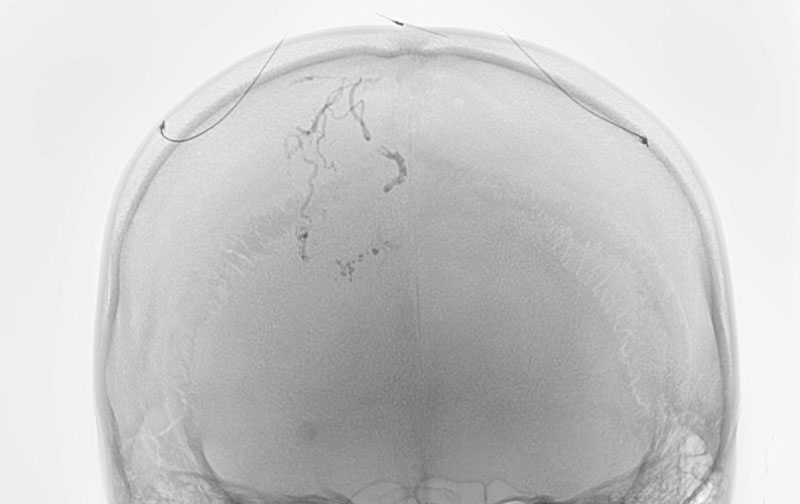

No.1620 手術後